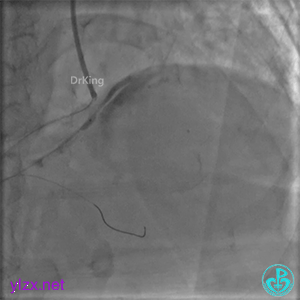

封堵后造影,PL分支远端血流中断。

心包内无明显积液。

术后超声未见心包积液。

1周后复查冠脉造影

PL主支通畅,远端一个小分支丢失,未见破口存在。